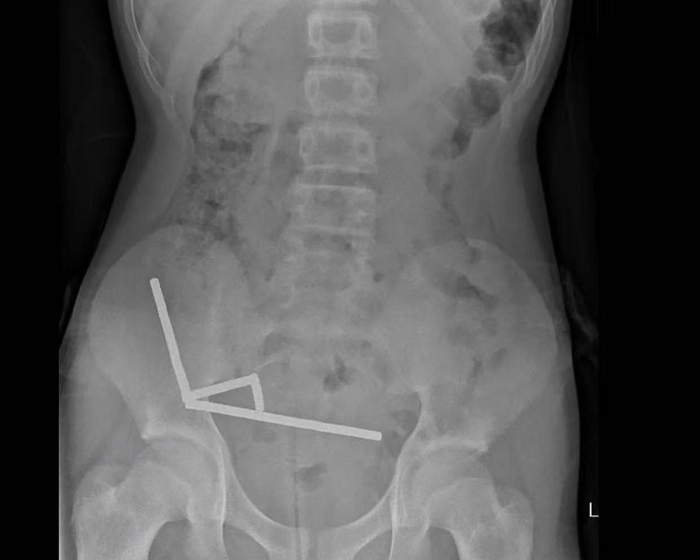

据悉,这名未透露姓名的少年在持续腹痛4天后被送往新西兰北岛的一家医院。医生通过X光检查发现,这些磁铁在他的肠道内互相吸附,形成了四条链状结构。

据该院医生于周五在《新西兰医学杂志》上发表的报告称,外科医生取出了磁铁并切除了部分受损的肠组织。磁铁的吸力导致男孩小肠及盲肠(属大肠的一部分)出现四处组织坏死。该男孩在住院8天后康复出院。

医生介绍,男孩大约一周前吞下了80至100颗大功率钕磁铁,每颗尺寸为5×2毫米。报告称,这些磁铁通过一家跨境电商平台购买。